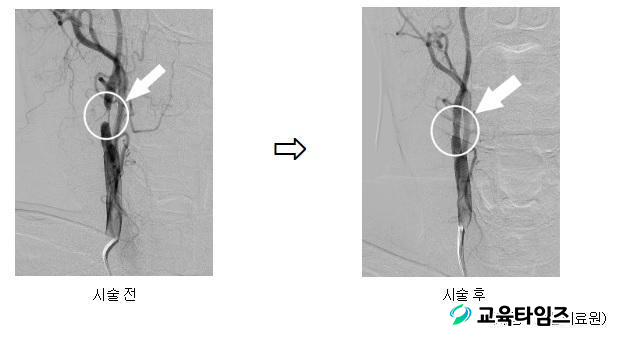

ÀÀ±ÞÀÇ·á¼¾ÅÍ¿¡¼ Á¤¸ÆÇ÷Àü¿ëÇØÁ¦¸¦ Åõ¾à ÈÄ ½Å°æ°ú(ÆÄ°ß±³¼ö ÀÌÀÀÁØ)·Î ÀÔ¿øÇÏ¿© 28ÀÏ ³ú ÀÚ±â°ø¸íÇ÷°üÁ¶¿µ¼ú(MRA) °Ë»ç¸¦ ½ÃÇàÇÏ¿´´Ù. MRA °Ë»ç °á°ú ¿ìÃø °æµ¿¸ÆÀÇ ½ÉÇÑ ÇùÂøÀÌ °üÂûµÇ¾ú°í, ¾ÇÈ °¡´É¼ºÀÌ ³ôÀº »óȲÀ̾ú´Ù.

ÀÌ¿¡ ȯÀÚ ¹× º¸È£ÀÚ¿¡°Ô Ç÷°üÀ» ³ÐÈ÷´Â °æµ¿¸Æ¼ºÇü¼ú/½ºÅÙÆ® ½Ã¼ú ¼³¸í ÈÄ 6¿ù 30ÀÏ ¼¿ï Áß¾Ó´ëÇб³º´¿øÀ¸·Î Àü¿ø, 7¿ù 7ÀÏ ¿ìÃø °æµ¿¸Æ ÇùÂø º´º¯¿¡ ´ëÇØ Ç÷°ü ¼ºÇ÷¼ú ¹× ½ºÅÙÆ® »ðÀÔÀ» ½ÃÇàÇÏ¿´°í, 18ÀÏ Æ¯º°ÇÑ ÈÄÀ¯Áõ ¾øÀÌ ¿ÏÀüÈ÷ ȸº¹ÇÏ¿© Åð¿øÇÏ¿´´Ù.